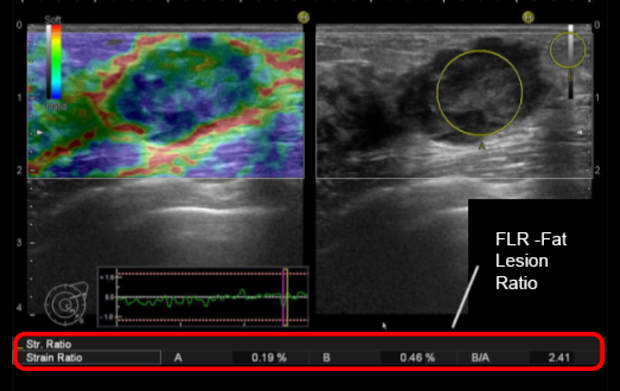

Technika obrazowania typu Strain Elastography (elastografia odkształceniowa/uciskowa) pozwala na wizualizację sztywności tkanek za pomocą mapy kolorów. Metoda ta może być stosowana w celu zwiększenia pewności diagnostycznej w różnicowaniu zmian łagodnych i złośliwych.

Od 2003 roku dodano wiele dodatkowych funkcji zwiększających dokładność i wiarygodność pomiarów, np. wykres odkształcenia, uśrednianie klatek, automatyczny wybór obrazu przy zamrożeniu, współczynnik odkształcenia i pomiary histogramu odkształcenia.

Elastografia odkształceniowa tkanek w czasie rzeczywistym (RTE)

RTE to innowacyjna metoda ultrasonograficzna umożliwiająca ocenę elastyczności tkanek. Stanowi ona nowatorskie narzędzie diagnostyczne do oceny i kolorowej wizualizacji elastyczności tkanek w czasie rzeczywistym. Ta metoda ultrasonograficzna kolejnej generacji znakomicie sprawdza się w diagnostyce chorób piersi, prostaty, tarczycy i trzustki. Tam, gdzie wskazana jest biopsja, RTE pozwala na dokładniejszą lokalizację zmian.

•    RTE pozwala na ekstrakcję danych o odkształceniu, zapewniając dostęp do pomiarów półilościowych za pomocą narzędzia Strain Ratio;